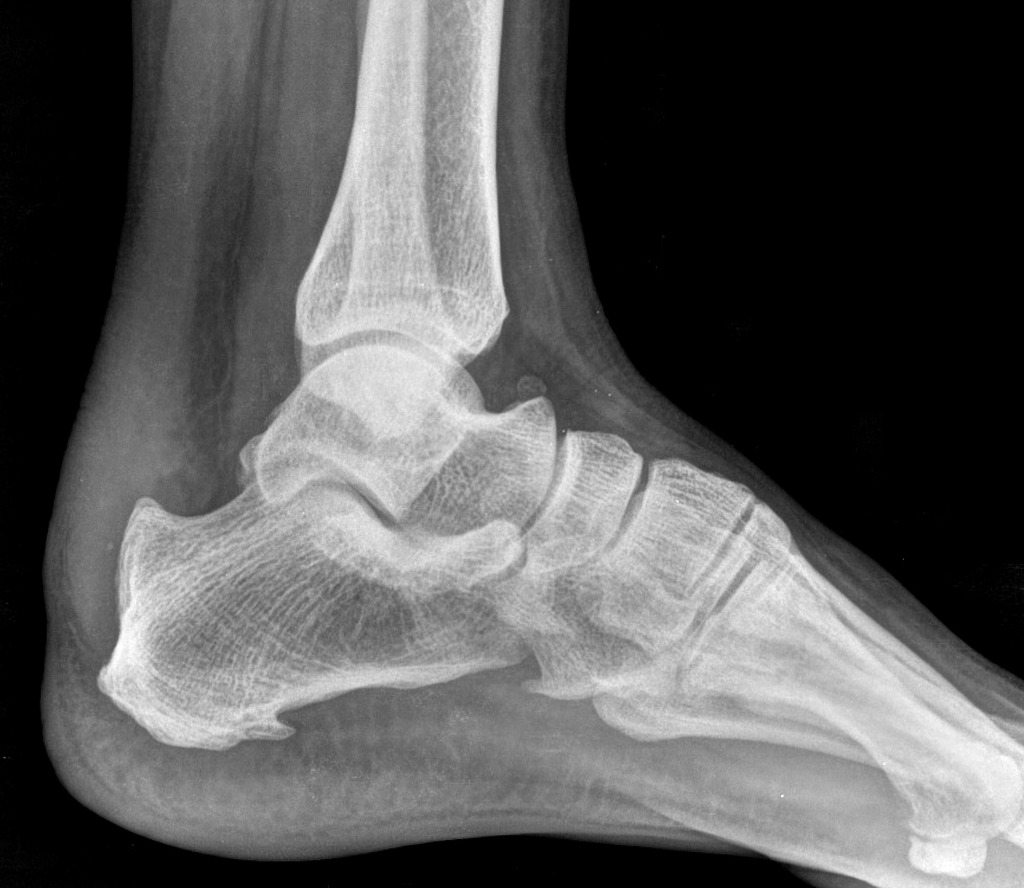

诊断方法包括病史询问、体格检查、X线和磁共振检查。X线主要评估骨质增生程度,明确有无其他足部畸形,例如高弓足。而磁共振检查可以显示跟腱和骨的关系、滑囊炎的进展程度,对制定手术方案具有一定帮助。